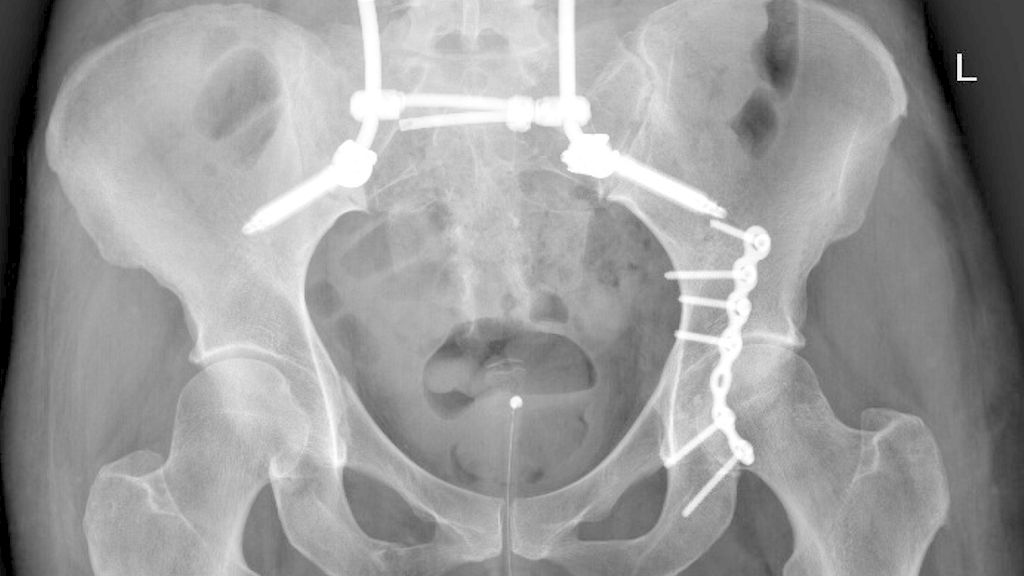

Abb. 2: Beckenübersicht einer 48-jährigen Patientin mit lumbopelviner Stabilisierung und Acetabulumplattenosteosynthese nach Sturz aus grosser Höhe mit lumbopelviner Dissoziation und mehrfragmentärer transforamineller Frakturkomponente, oberer und unterer Schambeinastfraktur rechts und Acetabulumfraktur links